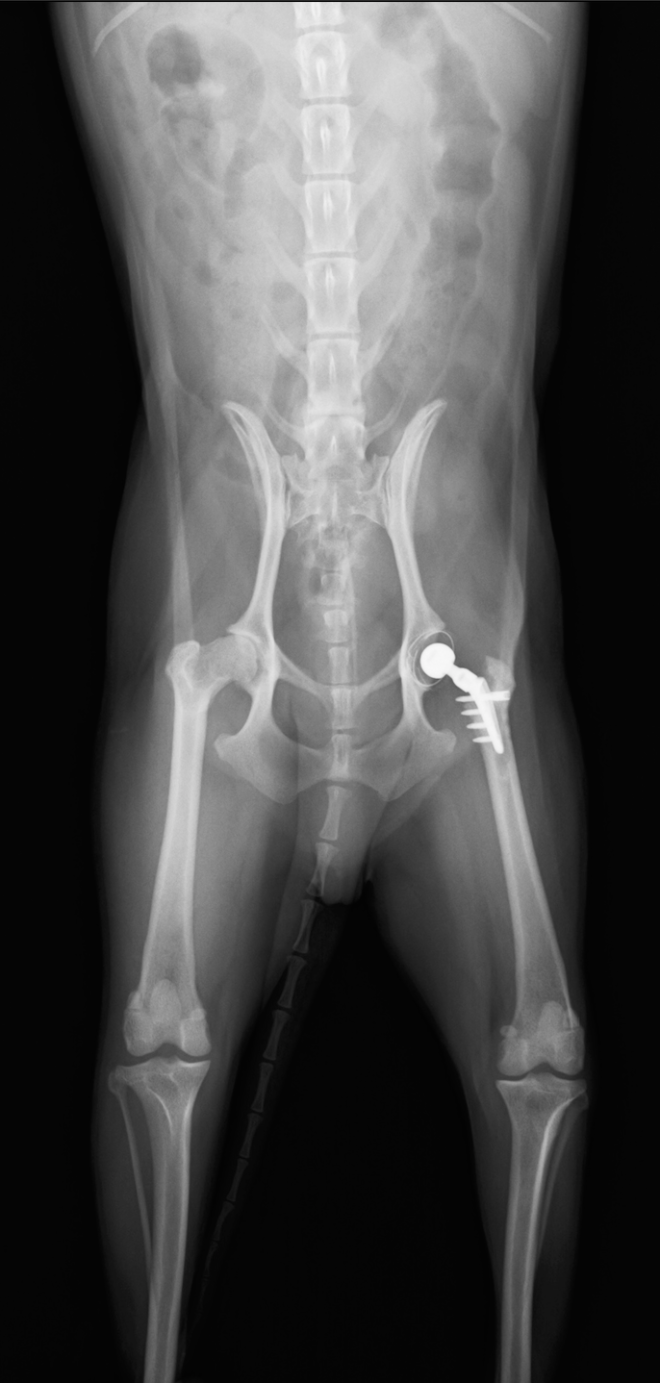

脱臼時のレントゲン画像

エーマースリング包帯後のレントゲン画像